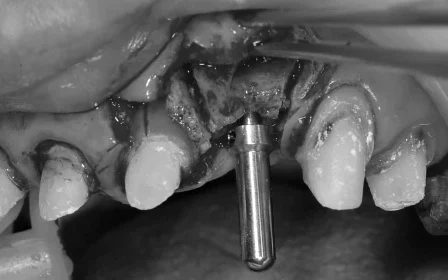

インプラント治療をするにあたり、まず骨幅を広げるために、歯茎を開き歯を支えている骨を慎重に縦に半分に分割し、その隙間にインプラントと骨を増やす材料を一緒に詰め歯茎を縫合する治療「スプリットクレスト」を行いました。

スプリットクレスト:違う角度からの写真で位置を確認しています。